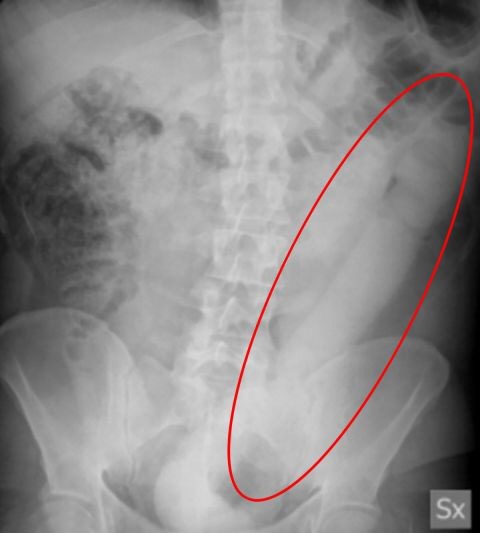

An X-ray revealed a 23 inch (60cm) object in his colon, according to the bizarre tale published in Case Reports.